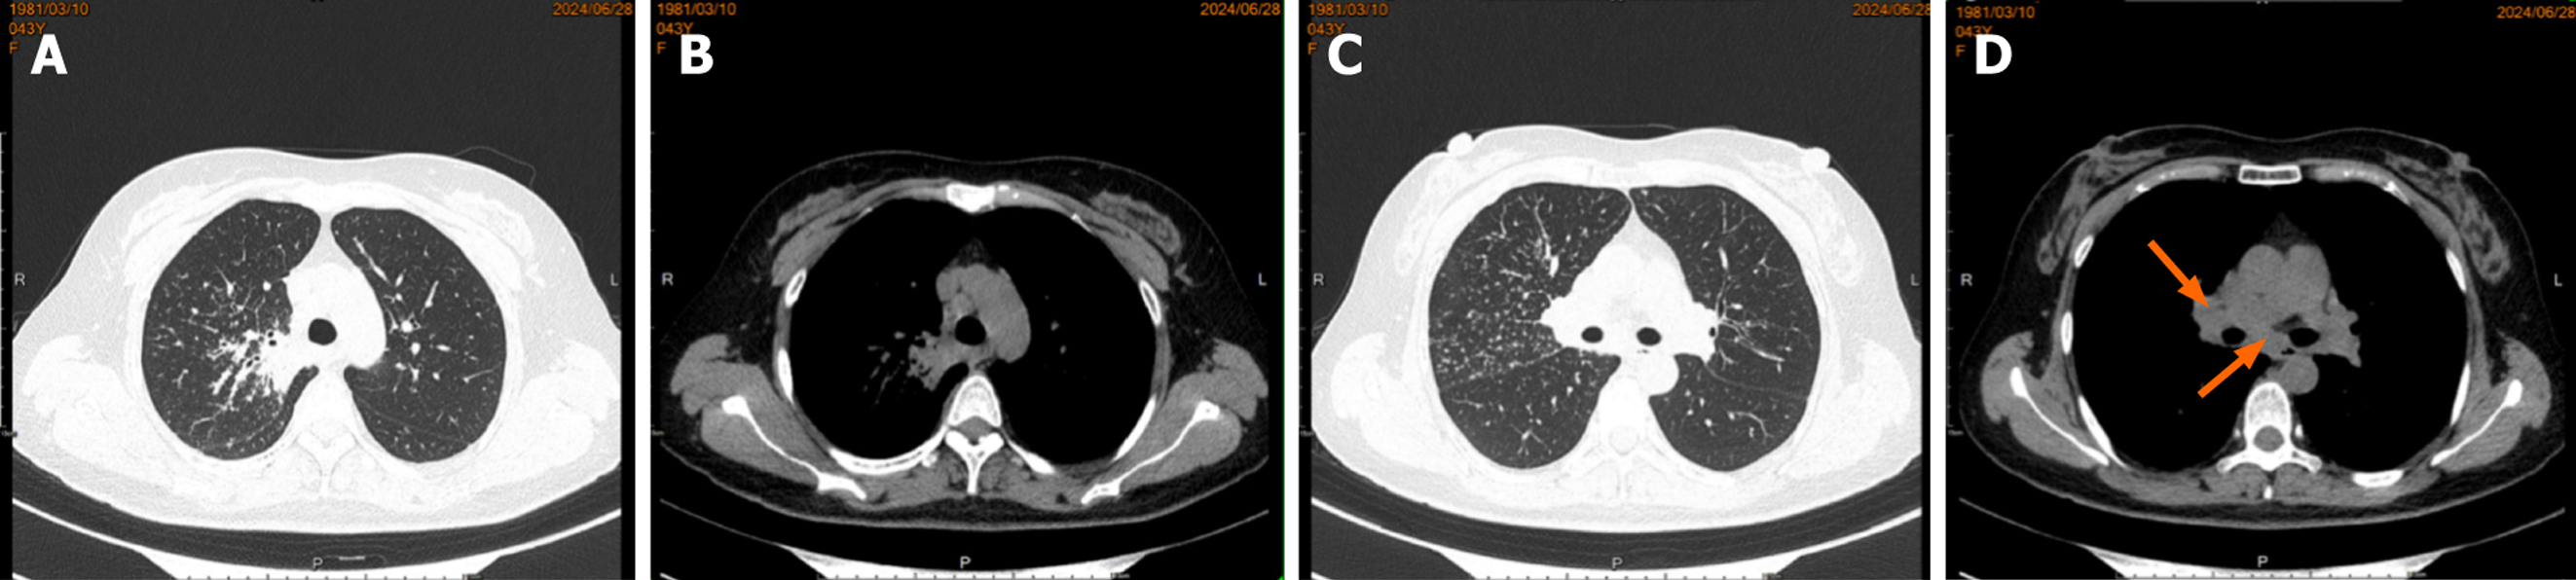

Case 1: Bronchoscopic lavage (June 7, 2024) showed no tumor cells. There were no remarkable results in initial diagnostic evaluations, including routine blood tests, erythrocyte sedimentation rate, biochemistry, coagulation profile, cardiac markers, and serum tumor markers. A repeat procedure was performed on July 1, 2024, under informed consent due to inconclusive findings from the previous bronchoscopy. Bronchoalveolar lavage fluid analysis showed no pathogens but a lymphocyte count of 12002/μL and a CD4/CD8 ratio of 5.81. A biopsy of the right upper lobe apical segment lesion was obtained, followed by EBUS-TBNA using an Olympus 21-G needle to sample station 7 Lymph nodes and posterior upper tracheal soft tissue (Figure 1). Subsequently, EBUS-TBFB was conducted by inserting a 1.2-mm fine biopsy forceps through the pre-established 21-G puncture site under real-time ultrasound guidance. As a result, 4-6 mediastinal biopsies with specimens ≥ 3 mm in diameter were obtained. No post-procedural bleeding was observed. There were scattered epithelial cells, inflammatory infiltrates, and multinucleated giant cells, but no atypia or granulomas in the histopathological analysis of EBUS-TBNA specimens, whereas EBUS-TBFB samples confirmed non-caseating granulomas with multinucleated giant cells (Figure 2A). Immunohistochemistry demonstrated Cytokeratin pan (epithelial+), CD68 (KP-1+), S-100 (−), and Ki-67 (high expression in inflammatory cells), while special stains for acid-fast bacilli, periodic acid-schiff, and Gomori methenamine silver were negative. Serum angiotensin-converting enzyme levels were elevated at 76.3 U/L.

Case 1: A routine chest CT 20 days earlier had revealed a right lung shadow. Subsequent contrast-enhanced chest CT (June 6, 2024) at an external hospital demonstrated a hypervascular right hilar mass with surrounding obstructive pneumonia, scattered enlarged mediastinal lymph nodes, and right pleural effusion. PET-CT suggested malignancy in the right upper lobe with possible pleural involvement, lymphangitic carcinomatosis, and metastases to bilateral hilar/mediastinal lymph nodes (June 17, 2024; Figure 3). In addition, multiple subpleural lung nodules with low metabolic activity were observed. A repeat contrast-enhanced chest CT on June 28, 2024, confirmed a 2.7 cm × 2.0 cm irregular, heterogeneous mass in the right upper lobe, accompanied by obstructive pneumonia and enlarged right hilar and medi